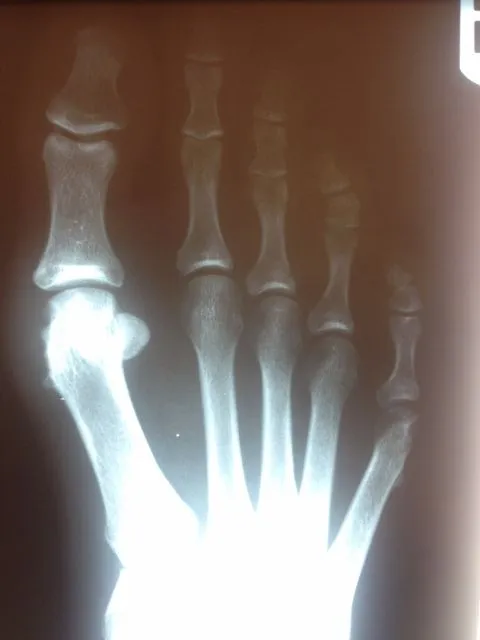

In the x-ray image below is a Hallux Valgus or what is more commonly known as a bunion deformity where the great toe is deviated towards the lesser toes causing abnormal structure which is a result of genetics, abnormal shoegear and abnormal mechanics will cause wearing of the joint and enlargement of the head of the long bone called the first metatarsal.

Post-surgical repair of the same patient bunion deformity with the great toe now in rectus (straight) position with surgically placed screws in the head of the first metatarsal that were used to secure fixation of the cut made across the bone to translate the head of the bone laterally in order to reduce the deformity. The screws will remain in place even after the bone heals.